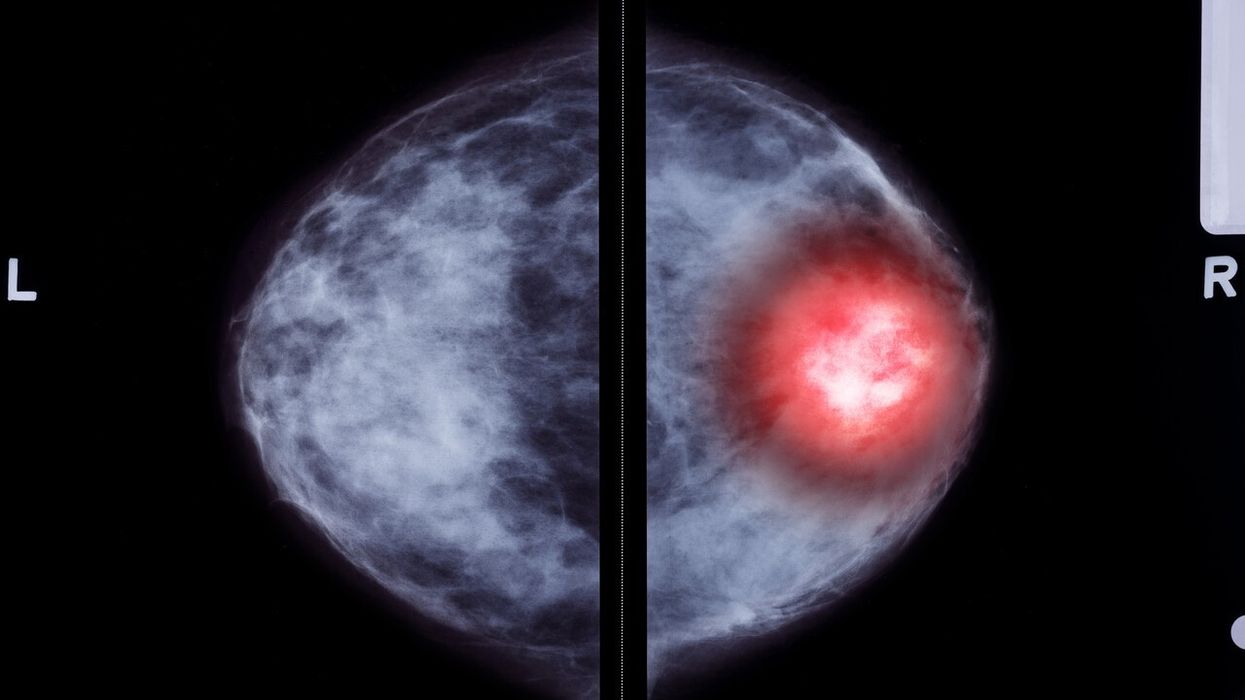

Tucatinibi, si shtesë e terapisë, vonon përparimin e sëmundjes te kanceri metastatik i gjirit HER2-pozitiv

Shtimi i tucatinibit (Tukysa) në terapinë e mirëmbajtjes së linjës së parë me trastuzumab (Herceptin) dhe pertuzumab (Perjeta) vonoi progresionin e sëmundjes te pacientet me kancer metastatik të gjirit HER2-pozitiv, duke zgjatur potencialisht kohën pa kimioterapi. Këto janë rezultatet e studimit klinik të fazës III HER2CLIMB-05, të prezantuara në Simpoziumin për Kancerin e Gjirit në San Antonio, i mbajtur nga 9 deri më 12 dhjetor 2025. Rezultatet e këtij studimi u publikuan njëkohësisht në revistën Journal of Clinical Oncology.

Kanceri i gjirit HER2-pozitiv përbën rreth 17 për qind të të gjitha rasteve të kancerit të gjirit dhe lidhet me një normë pesëvjeçare mbijetese më të ulët se 50 për qind te pacientet me sëmundje metastatike. Që nga viti 2012, terapia e linjës së parë për kancerin metastatik të gjirit HER2-pozitiv ka mbetur kryesisht e pandryshuar dhe përbëhet nga kimioterapia e ndjekur nga terapia e mirëmbajtjes me dy antitrupa monoklonalë anti-HER2, deklaroi dr. Erika Hamilton, drejtoreshë e kërkimeve për kancerin e gjirit në Sarah Cannon Research Institute në Nashville, transmeton Telegrafi.